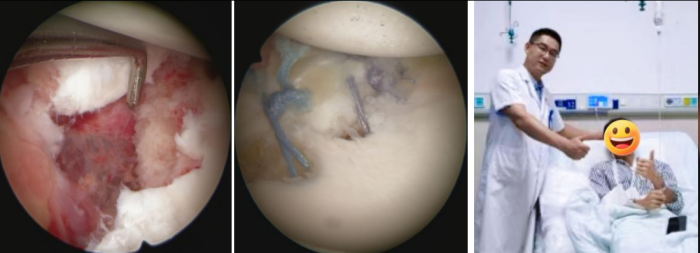

术前CT示肩胛盂前下方骨折(Bony bankart损伤)

考虑到患者年轻且有强烈的运动需求,运动医学科团队为他实施了关节镜下微创修复手术。通过三个几毫米的小切口,精准地将撕脱的骨折块和盂唇组织复位到原位,并将它们牢固地重新固定在了肩胛盂上,恢复了肩关节稳定性结构,患者术后恢复良好,现已进入个性化的康复阶段。

关节镜下微创修复手术,患者术后恢复良好